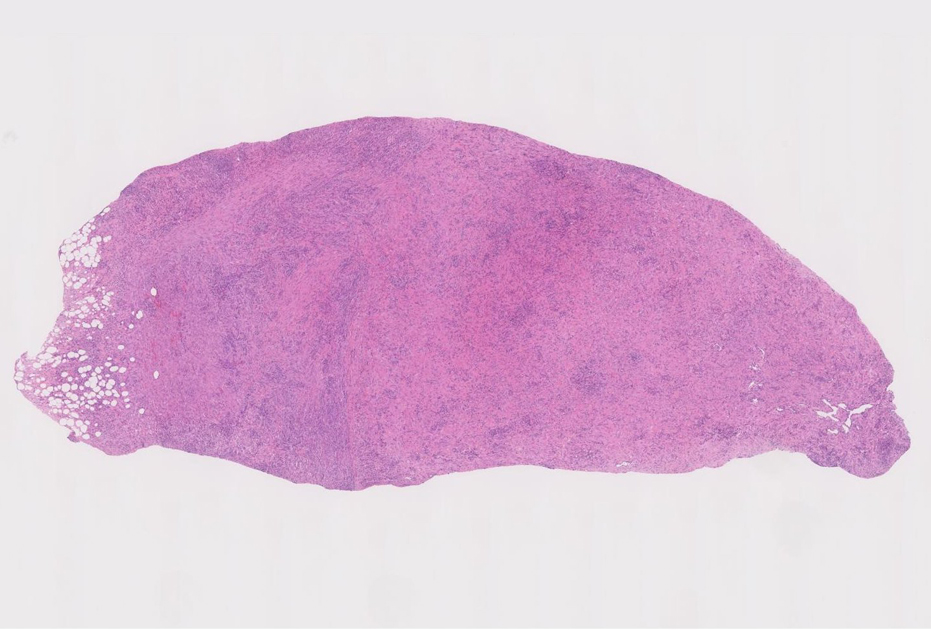

膵尾部, 骨盤腔内腹膜腫瘤生検組織所見

膵尾部の腫瘤

膵腫瘤針生検組織片(クリックで大きな画像が見られます)

腹膜腫瘤の針生検組織片

組織像は膵腫瘤B, Cと同じくinflammatory myofibroblastic tumorである。島状に形質細胞主体の慢性炎症が強い。腹膜腫瘤には腺管は認められない。